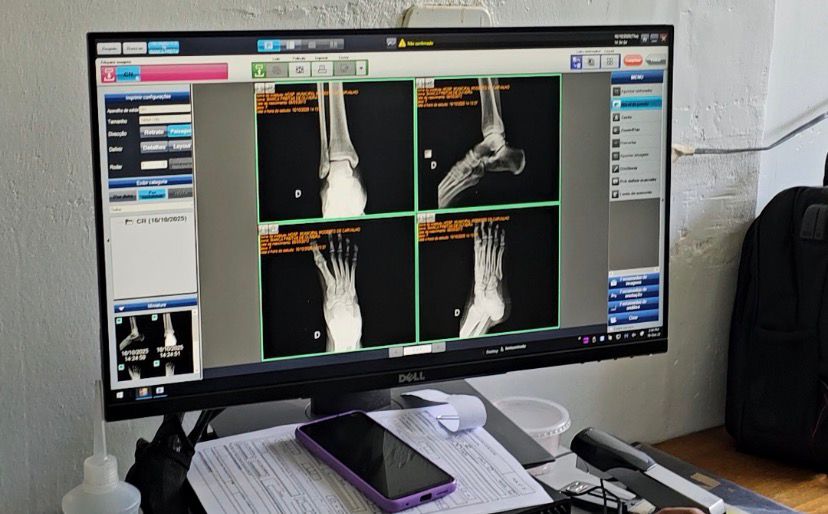

No HMMC, são feitos, por mês, mais de três mil exames de raio x. Com o novo aparelho, digital, as imagens devem ser disponibilizadas, para o médico, em cinco minutos, agilizando os diagnósticos.